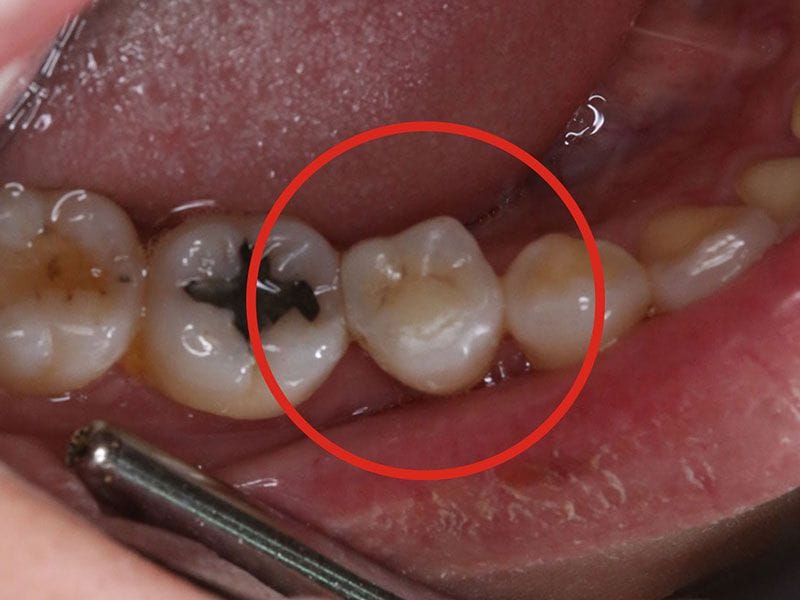

除汞完成

1. 3D齒雕--- 較淺的缺損我們建議用3D齒雕修復,不僅美觀,且強度更高